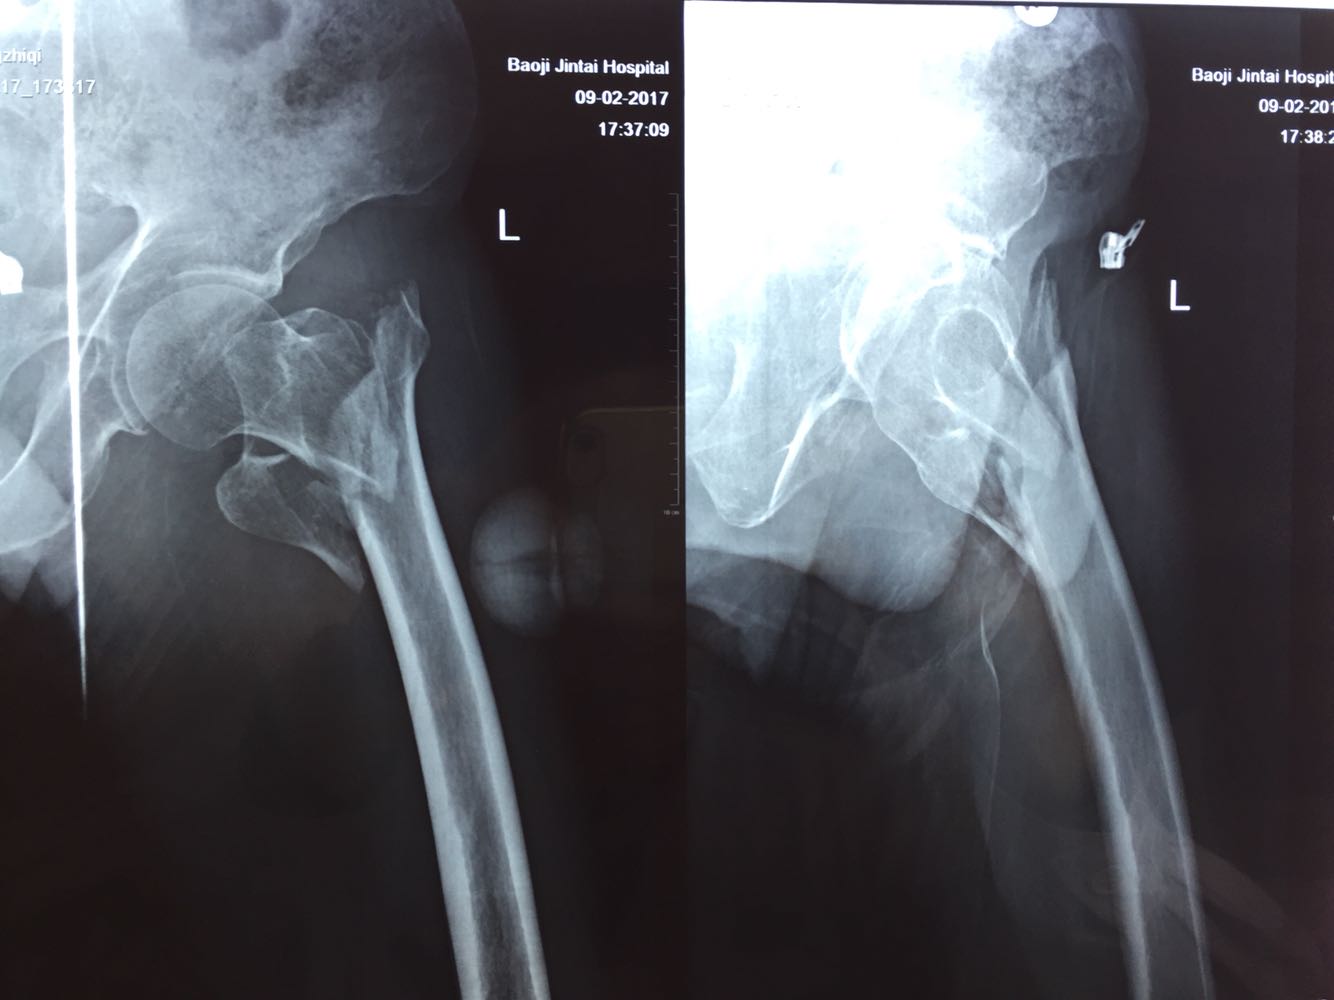

左股骨粗隆间骨折